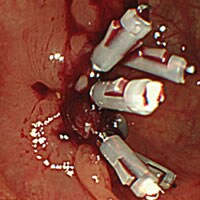

当日ポリープ除去手術が可能です

診断から治療まで一貫して対応ができるため、検査の際に万が一、ポリープを発見した際には即日の切除手術を行うことも可能です。

大腸ポリープ切除

内視鏡での観察中に大腸ポリープが見つかることがありますが、ポリープを速やかに切除することに

なった場合、少し検査時間が延長されますのでご了承ください。

(ポリープ1個の切除に、5~10分の時間を要します)検査終了後